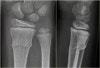

**X-ray :**녹색 줄기 골절(Greenstick fracture)